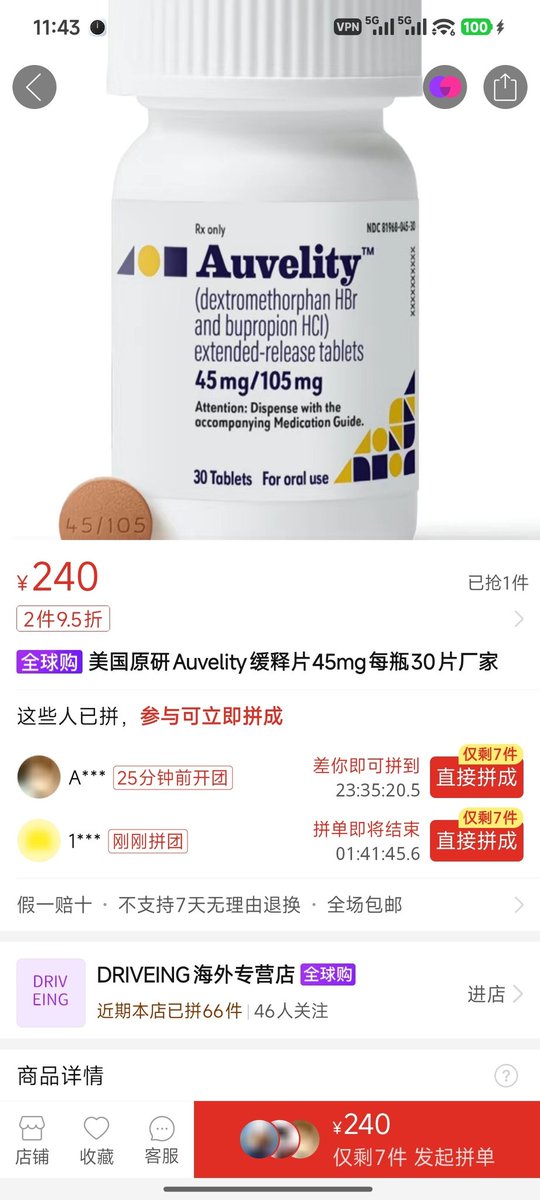

好家伙唑吡坦又骗我吃药了还顺带上了个失忆状态,这下子知道是谁干的了。吃auv之后dxm清除得特别慢...让我感觉要从此告别了的程度,加上我基因检测本来cyp2d6就是中速代谢,这个尾巴就被拖的特别长